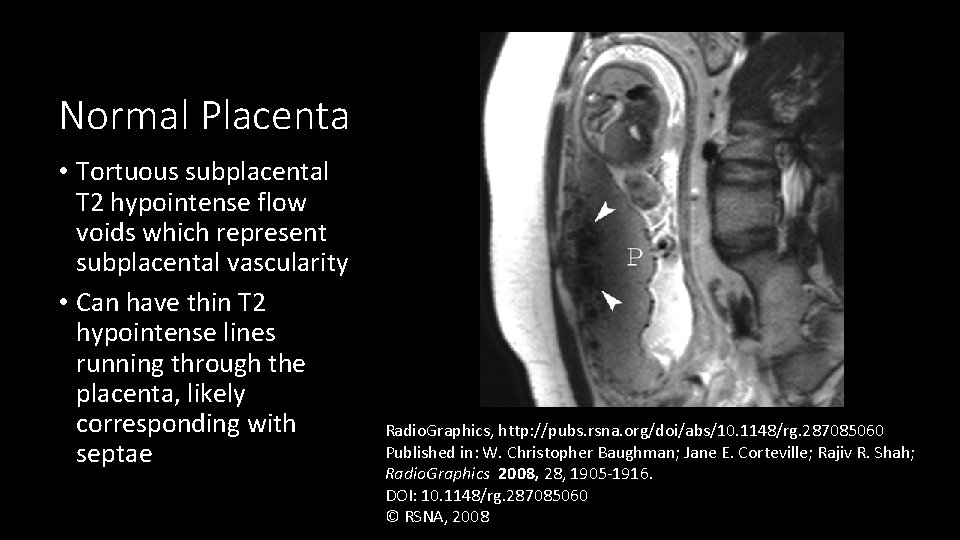

Normal Placenta • Tortuous subplacental T 2 hypointense flow voids which represent subplacental vascularity • Can have thin T 2 hypointense lines running through the placenta, likely corresponding with septae Radio. Graphics, http: //pubs. rsna. org/doi/abs/10. 1148/rg. 287085060 Published in: W. Christopher Baughman; Jane E. Corteville; Rajiv R. Shah; Radio. Graphics 2008, 28, 1905 -1916. DOI: 10. 1148/rg. 287085060 © RSNA, 2008